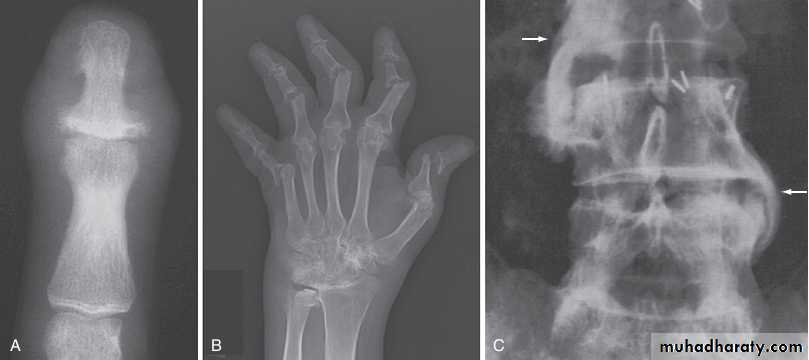

In established AS, radiographs of the sacroiliac joint show irregularity and loss of cortical margins, widening of the joint space and subsequently sclerosis, joint space narrowing and fusion.

Lateral thoracolumbar spine Xrays may show anterior ‘squaring’ of vertebrae due to erosion and sclerosis of the anterior corners and periostitis of the waist.

Bridging syndesmophytes may also be seen. These are areas of calcification that follow the outermost fibres of the annulus

Investigations

In advanced disease, ossification of the anterior longitudinal ligament and facet joint fusion may also be visible. The combination of these features may result in the typical ‘bamboo’ spine.

In chronic or recurrent disease, Xrays show periarticular osteoporosis, joint space narrowing and proliferative erosions.

Another characteristic feature is periostitis, especially of metatarsals, phalanges and pelvis, and large, ‘fluffy’ calcaneal spurs.

In contrast to AS, radiographic sacroiliitis is often asymmetrical and sometimes unilateral, and syndesmophytes are predominantly coarse and asymmetrical, often extending beyond the contours of the annulus (‘nonmarginal’)